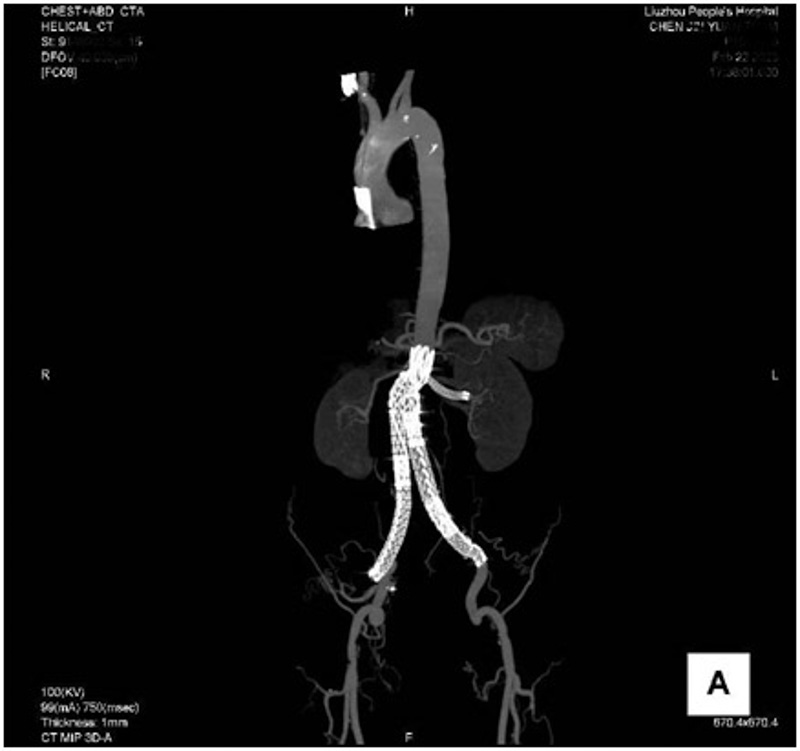

術(shù)中,手術(shù)團(tuán)隊(duì)根據(jù)術(shù)前薄層CT斷面,測(cè)量腹主動(dòng)脈、腎動(dòng)脈直徑開(kāi)口角度、血管之間距離等數(shù)據(jù),在覆膜支架對(duì)應(yīng)的位置精確修剪“開(kāi)窗”,在DSA引導(dǎo)下將支架精準(zhǔn)釋放,并將“開(kāi)窗”部位精確對(duì)準(zhǔn)腎動(dòng)脈,既完美地保留了腎動(dòng)脈的血供,又成功將腹主動(dòng)脈瘤封堵。術(shù)后,陳老伯血管走行流暢,管壁光滑,成功解除了腹主動(dòng)脈瘤破裂的風(fēng)險(xiǎn)。

▲術(shù)后,腹主動(dòng)脈瘤隔絕良好,左腎動(dòng)脈通暢